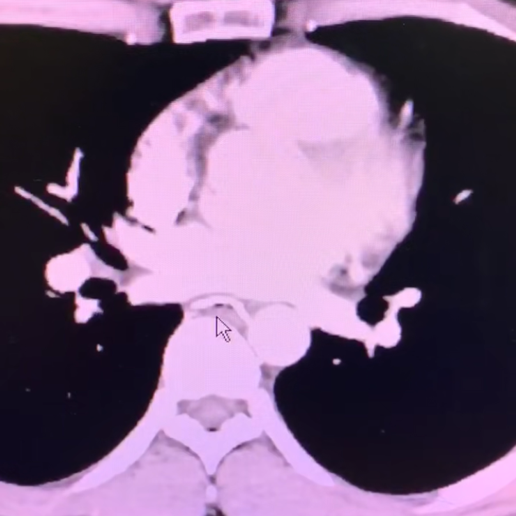

左上:鱼刺刺破食管左侧壁,紧贴主动脉